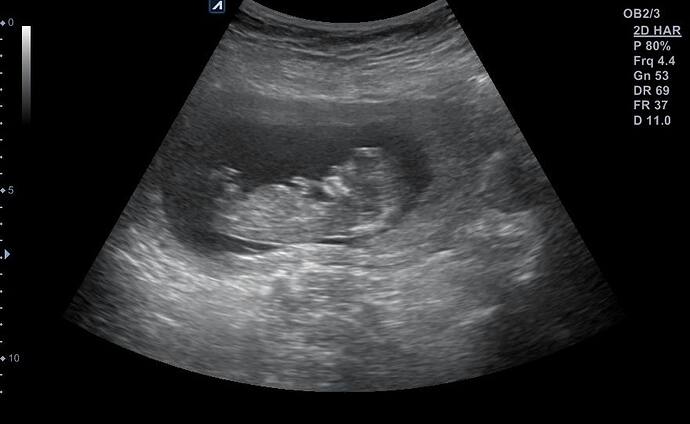

Aynı benimkine benziyo bana kız dediler sorduğumda bizde emin değiliz diyolar bakalm hayırlısı kız diye biliyorum

Chat gpt sordun mu bana seninki net kız gibi geldi ama kendime fikir yürütemiyorum

Nub teorisine göre yorumla de

Şimdi sordum çok net değil ama kız gibi dedi bu çok öncesinin fotoğrafı 12 haftalıkken çekilmişti en son olan fotoğraf doktorun kendisinde bakalm bu sefer daha net söyler inşAllah

Kız bence ya

Erkek gibi duruyo canim Allah bilir yine de boylu boyuna da yatiyo maaşallah Rabbim sağlıklı sıhhatli kucagina almak nasip etsin insallah canım

Erkek bebiş kuzum

Erkek gibi geldi bana da hayırlısını versin rabbim insallah canim allah sag salim sağlıklı bir sekilde kucagina almak nasip etsin insallah